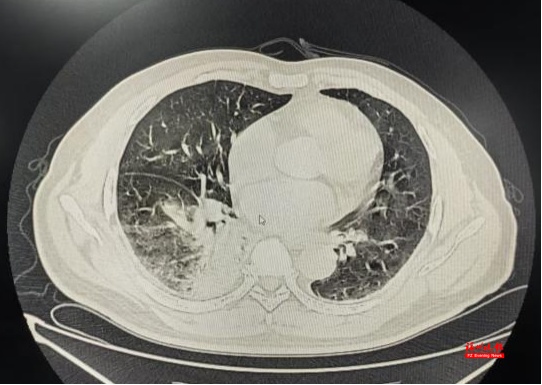

“会不会是鼠咬热?”林秀华心里打了个问号。但结合患者的肺部CT显示右下肺炎症,以及长期接触家禽的经历,她怀疑可能另有“真凶”。

最终确诊为鹦鹉热衣原体肺炎

吴先生住院期间就先后出现了肝损伤、肺炎加重。“幸好诊断明确后立即调整了治疗方案,两周后,吴先生病情渐渐好转了。”林秀华主任介绍,鹦鹉热如果诊断及时、治疗规范,预后一般良好;但如果延误治疗,病死率可达15%~20%。